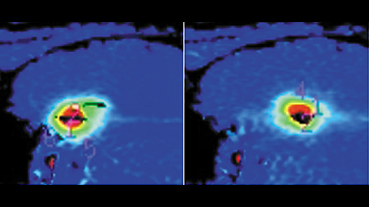

Innovative technologies and alternatives to traditional treatments are transforming the diagnosis and management of neurological conditions. In 2025, NewYork-Presbyterian physicians and surgeons from Columbia and Weill Cornell Medicine used sonication and convection-enhanced delivery to penetrate the blood-brain barrier, validated an adjunctive treatment for subdural hematoma, broadened access to spine surgery, advanced experimental therapies for neurodegenerative diseases, and more. Our specialists have been steadfast in reshaping the fields of neurology and neurosurgery in the pursuit of better patient outcomes and enhanced quality of care.

From cutting-edge research to compassionate patient practice, neurologists and neurosurgeons from Columbia and Weill Cornell Medicine are at the forefront of developing and applying the most advanced approaches to treat debilitating conditions affecting the brain and spine. With a broad range of focus on neurodegenerative and neurovascular disorders to malignant tumors, our innovative and advanced care is leading to new treatment options and enabling patients to achieve the best possible outcomes.